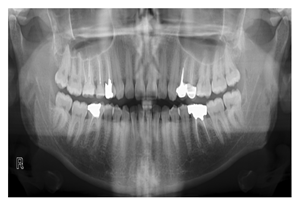

| Panoramic X-Rays | [4,11,20,22,23,24,26,27,30,31,32,43,44,57,58,60,61,62,63,66,68,69,89,105,106,107,108,109,110,111,112,113,114,115,116,117,118,119,120,121,122,123,124,125,126,127] | Full visualization of jaw, such as tumors, teeth included, infections, post-accident fractures, temporomandibular joint disorders | ![]() | Captured outside the mouth which makes them more acceptable for the patient, they cause a lower infection rate, and lower radiation exposure, they are simple to apply and require less time but they are the most challenging type due to uneven lighting, the presence of noise and low resolution. |